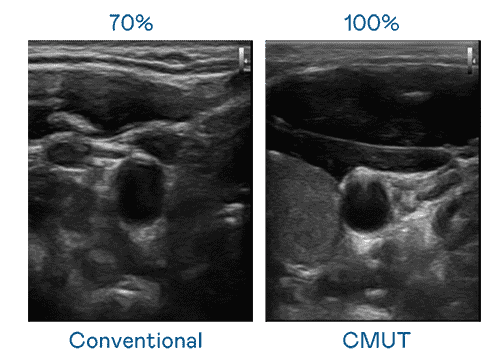

CMUT 技术是一种用电容式微机电元件来产生超音波讯号的技术。。。与传统 PZT 压电式技术相比,,,,CMUT 频宽增加 30%,,更宽频的超音波讯号让影像解析度大幅提升,,,是实现高影像品质医疗超音波扫描、、、促进精准医疗发展的关键技术。。

大频宽带来超清晰影像

超音波影像的解析度高低,,,,首先取决于探头能发出的讯号频宽。。。至成国际 CMUT 可提供高清晰的超音波讯号,,,,提供高频宽、、、、高灵敏度、、影像纹理细节更高的超音波影像,,协助医护人员缩短影像判读时间及利用精准的医疗影像进行诊断。。。。